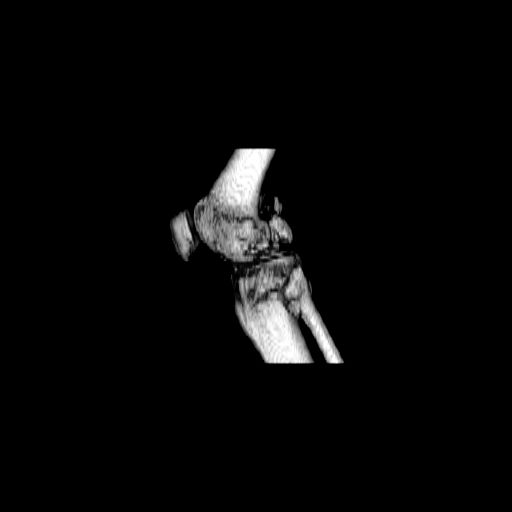

CT shows major bony fragments which are markedly rotated .With this amount of bony damage,you probably should attempt to get reasonably loooking knee with ORIF and thn if he needs a TKR due to pain a few years from now, then tleast you have something looking like a knee that you can replace rather than having to use revision knee for a primary TKR now. 4 weeks is not too long .what is the condition of soft tissues?

При внутрисуcтавных переломах трехмерные (3D) изображения, кроме красивого снимка, не дают полную информацию о состоянии отломков, самыми информативными являются корональные срезы на КТ и обычная длинная ренгенограмма конечности для сравнения оси конечности.

Фронтальные внутрисуставные переломы мыщельков бедра, так называемые Hoffa fracture, не частые, но встречающиеся переломы, в основном они связаны с травмой высокой энергией.

Даже при сросшемся переломе мыщелка рекомендуется реконструктивная операция для предотвращения последующих варус или вальгус деформации.

Место образовавшего костного дефекта после разворота мышелка заполняется спонгиозной аутокостью. Костная пластика применяется даже

в свежем случае.

Под наркозом редрессация, ранняя разработка сустава после операции, нагрузка на конечность через 12 недель помогут удержать без коллапса

фиксацию и поможет больному восстановить функции конечности без артропластики коленного сутава.